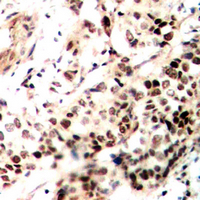

- Experimental details

- Immunohistochemical analysis of SMRT staining in human breast cancer formalin fixed paraffin embedded tissue section. The section was pre-treated using heat mediated antigen retrieval with sodium citrate buffer (pH 6.0). The section was then incubated with the antibody at room temperature and detected using an HRP conjugated compact polymer system. DAB was used as the chromogen. The section was then counterstained with hematoxylin and mounted with DPX.